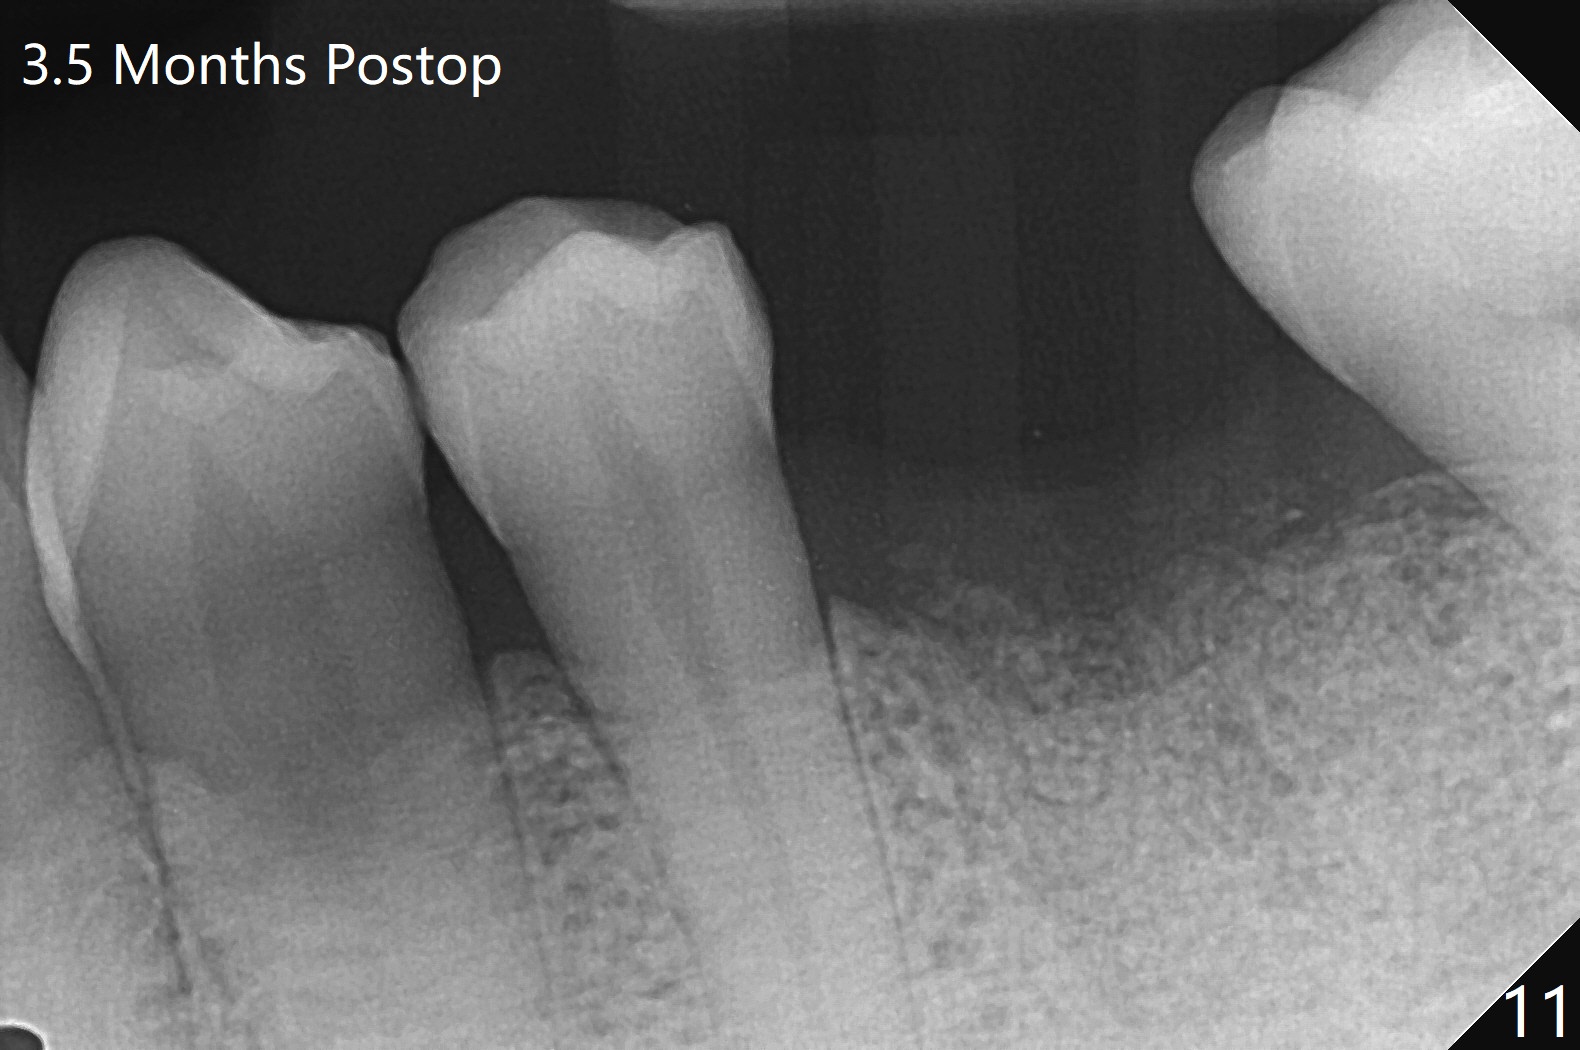

When the patient returns for #15 comp, the bone resorption and swelling at #19 are worse than those 3 years ago (Fig.1,2). After debridement, the mesial socket is large, while the septum is thin, irregular and with undercut (Fig.3). It seems difficult to obtain primary stability for an immediate implant. Vanilla bone and cortical bone hydrated with GEM21 S are placed for socket preservation (Fig.4,5), followed by 12x12 mm BioXclude and 4/0 PGA. In fact the bone height is limited for an immediate implant (Fig.6 (5x10 mm)). There is not enough bone in the septum for primary stability (Fig.7 (cross section of 3D image; L: lingual)). The socket heals 16 days postop (Fig.8). It appears that the granulation tissue is covered by a thin layer of granulation tissue (Fig.9 *), while the membrane remains in place (M). In fact the bone graft remains in the soft tissue zone as well as the hard tissue one (Fig.10). In spite of no apparent loss of bone graft (Fig.4,10), the graft seems to shrink in height 3.5 months postop (Fig.11), while the crest decreases (compare Fig.1 and 11). The keratinized gingiva is wide, but the alveolus reduces in width (Fig.12). The buccal crestal bone is lost 3.5 months postop (Fig.13).